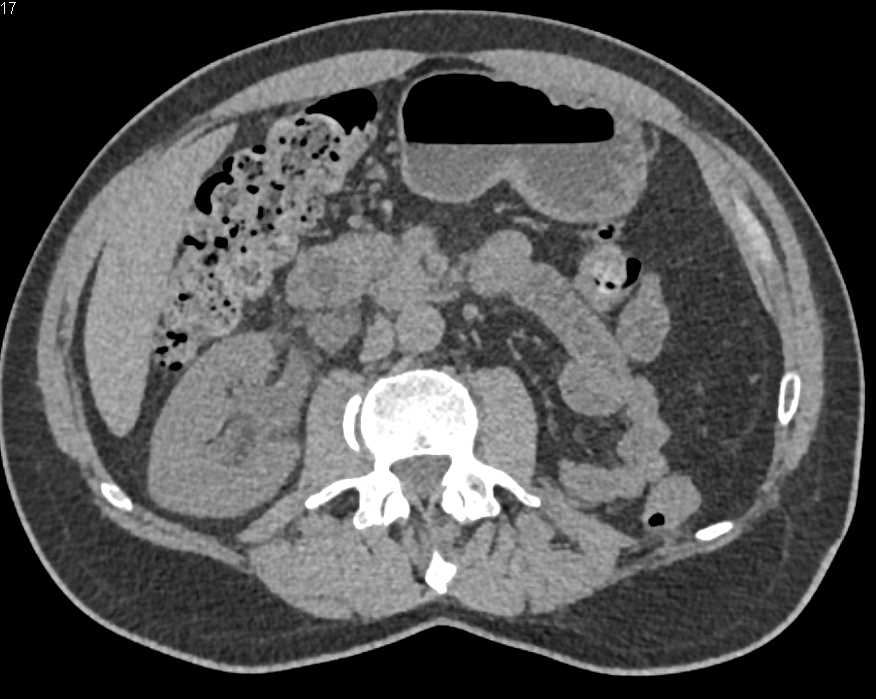

Acute Pyelonephritis Right Kidney